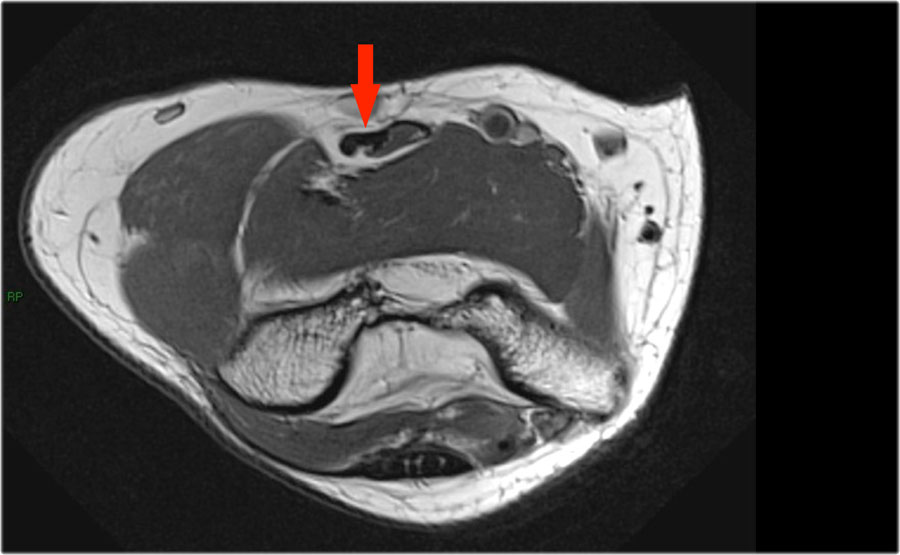

Những hình ảnh này của một nam giới 23 tuổi bị ngã chống tay khi đang trượt ván hai tuần trước.

Khi khám lâm sàng, ghi nhận giảm biên độ vận động khớp khuỷu và đau khi ấn dọc theo mặt ngoài.

Cấu trúc nào nằm phía sau chỏm quay trên hình ảnh cắt ngang?

Sagittal view:

- Một lần nữa, hình ảnh đặc trưng của phù tủy xương thường gặp trong trật khớp khuỷu tay ra sau với vết dập ở phía trước của chỏm xương quay (mũi tên đỏ) và ở phía sau của chỏm con xương cánh tay.

- Chỏm quay phải đã va chạm vào phần sau của chỏm con xương cánh tay.

Cấu trúc phía sau chỏm quay là dây chằng vòng.

Nó không đều và dày lên do hậu quả của trật khớp ra sau.